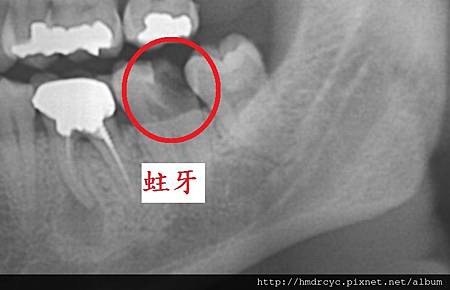

就是俗稱的水平智齒

當智齒長歪頂到前面的牙齒

細菌跑進來的時候會無法清潔

頂到前面牙齒的地方會蛀牙

而牙肉包住的地方會牙肉發炎牙周病